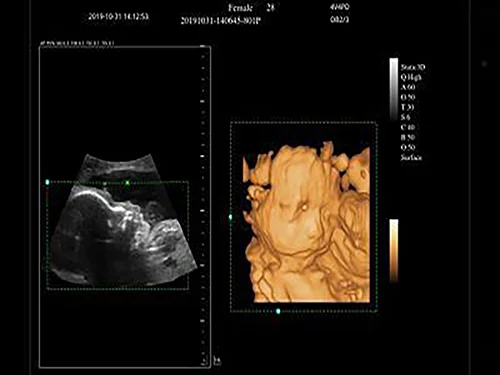

3D/4D-визуализация при использовании объёмных датчиков

Объёмный датчик 4V4CDS

• Рабочая полоса частот: 1,6–8,0 МГц

• Количество элементов: 128

• Применение: 3D/4D в акушерстве, 3D-визуализация абдоминальных структур.

4. Акушерство и гинекология

Объемное сканирование (4D, Real-time 3D) Да